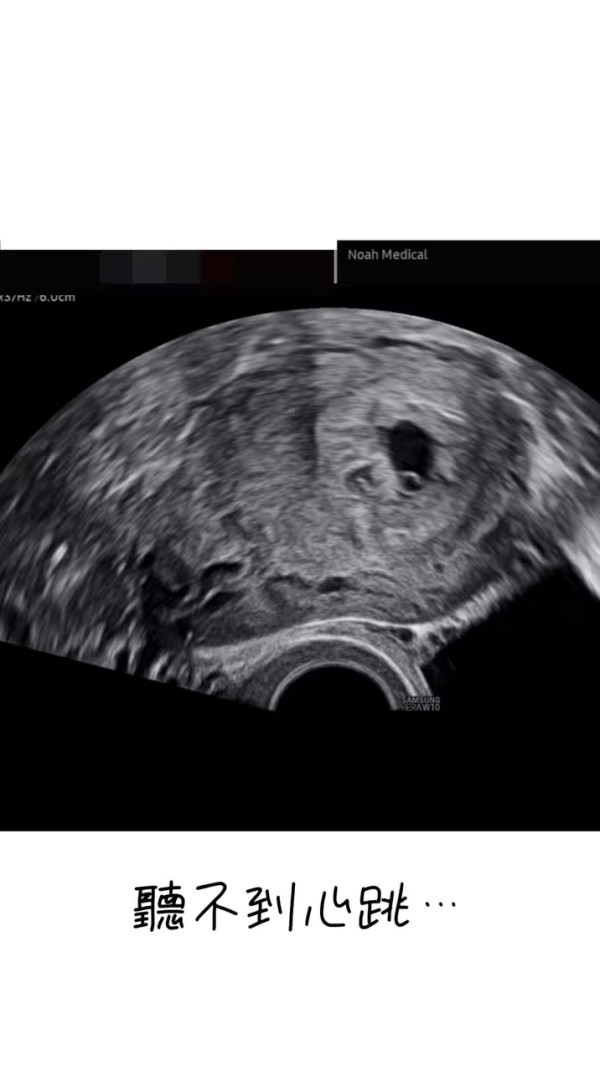

李清心只好耐心等待一星期後再檢查,不過等待的期間就令Katarina十分煎熬:「可惜(懷孕)周數太細喇,乜嘢都照唔到,聽唔到心跳,唯有休息一個禮拜等下次覆診睇吓有冇心跳啦。呢個禮拜真係好漫長,心情跌落谷底。」而她更晒出染有啡血及鮮血的衛生巾,表示持續有出血情況。